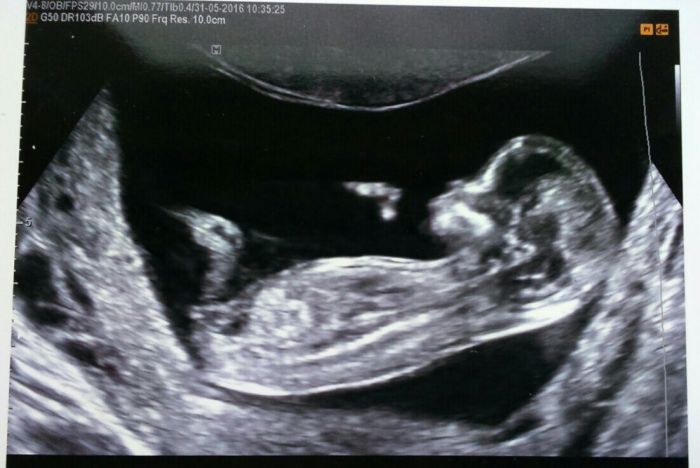

Tak jsem si včera byla pro tu krev a je v pořádku. Doktor mi udělal ještě rychlej ultrazvuk a taky dobrý. V úterý jedeme teda do ÚSTÍ. Strach se trochu zmenšil :-) Prý to vypadá na holčičku a už mám konečně fotečku našeho mimi.

já včera na screeaningu dopadla dobře. Riziko je vyšší jen kvuli věku. Jinak paní doktorka překontrolovala ručičky, nožičky prstíčky. Srdíčko,všechny organy.Projasnění a kustku v nosánku.Všechno bylo dobré. Akorát jedna céva nešla proměřit, miminko se k nám nechtělo natočit bříškem,tak nám trošku kazí hodnocení. Poslali mi ven běhat, ale stejně se nenatočilo. Na genetiku mi asi stejně pošlou. 8.6 jdu ke svému lékaři tak uvidíme.

[906559] Tak velká gratulaceSmile! Mimísek je krásnej...